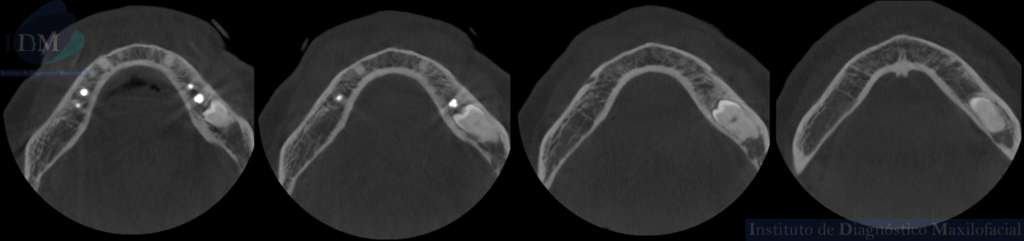

CORTES AXIALES

A la evaluación de la radiografía panorámica se evidencia reabsorción ósea alveolar bimaxilar, edéntulo parcial bimaxilar y presencia de múltiples implantes con prótesis sobre implantes así como tratamientos restaurativos. Siendo lo más destacado una molar retenida en cuerpo mandibular izquierdo, la cual esta mesioangulada.

Siendo así que en la tomografía volumétrica de haz cónico se evidencia una hipercementosis radicular, con los segmentos radiculares contactando con el conducto dentario inferior. Finalmente se evidencia un borramiento del espacio del ligamento periodontal compatible con anquilosis dentaria.